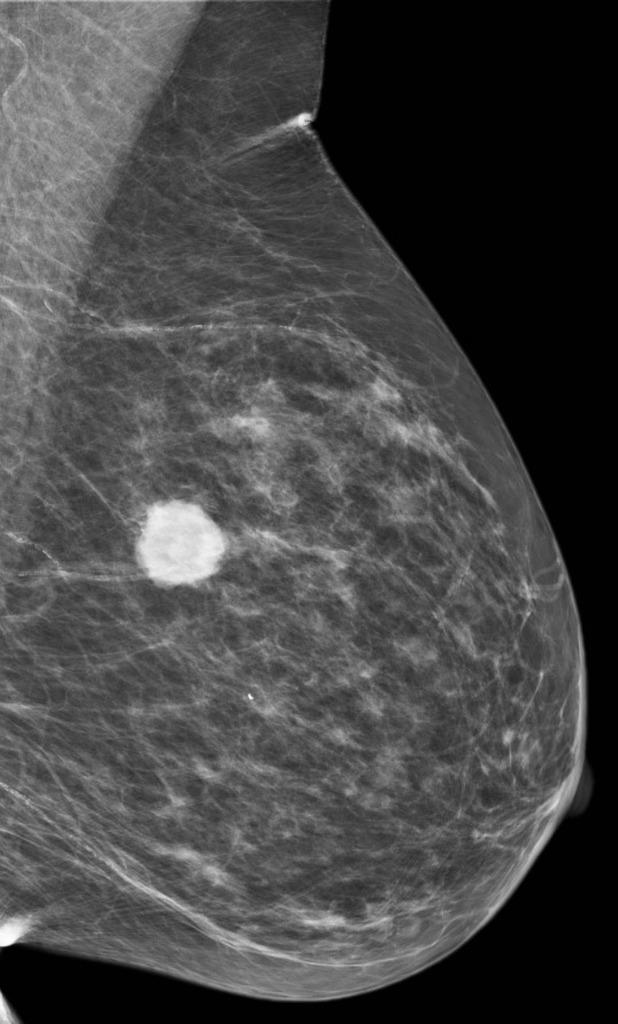

A mammogram of a breast showing a tumor in bright white against the normal breast tissue which appears grey. The tumor is dense and has both smooth, defined margins and spiculated edges.

Researchers are planning a phase 3 trial to test the anti-inflammatory drug L-NMMA to treat metaplastic breast cancer, a rare and often lethal form of the disease.

Credit: Courtesy of Dr. Garth Kruger

The treatment regimen shrank the tumors in approximately half of the patients in the study. (Based on historical data, the researchers estimated that about a third of the patients would have responded to chemotherapy alone.) Three patients with locally advanced breast cancer had all signs of their cancers go away following treatment.

Dr. Chang and her colleagues are planning an NCI-supported phase 3 clinical trial to test the drug in more patients. The study will include people with metaplastic breast cancer, a rare and often lethal form of the disease.